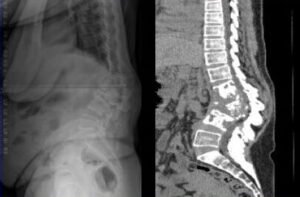

- Spinal Deformity

- Kyphosis is the most common deformity as the disease is mainly anterior although scoliosis is also seen

- Thoracic spine in involved in the majority of cases

- Deformity with active wet lesions have mobile apex more likely to collapse into a Kyphosis

- Deformity with healed dry lesions present with a rigid apex and slow progression

FOCOS Reviews